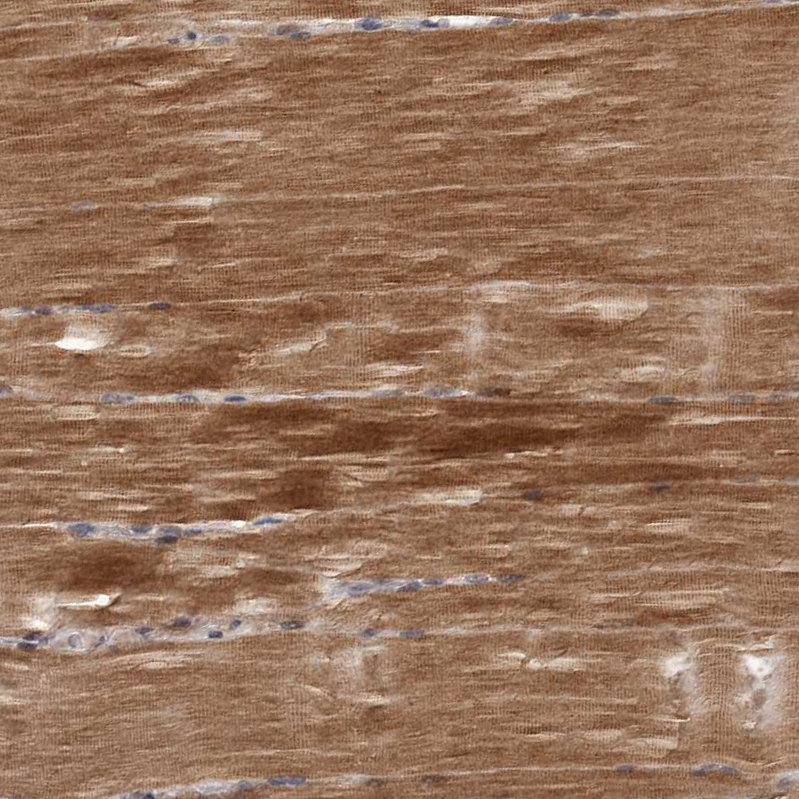

Immunohistochemical staining of human rectum shows strong cytoplasmic positivity in glandular cells.